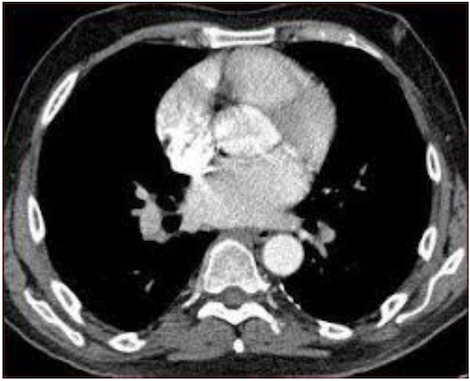

Streptococcus pneumoniae is goed voor 70-80% van de gevallen van meningitis. De sterfte bij pneumokokkenmeningitis wordt geraamd op 15% (en zelfs 33% bij patiënten die zijn opgenomen op een intensive care). De behandeling bestaat in een bètalactamantibioticum plus vancomycine in geval van hoge plaatselijke resistentie tegen penicilline. Linezolide en ceftaroline zijn ook mogelijk. Het wordt aangeraden een corticosteroïd toe te voegen om de sterfte te verlagen en de neurologische prognose te verbeteren, maar het nut ervan is niet bewezen bij patiënten die zijn opgenomen op een intensive care.